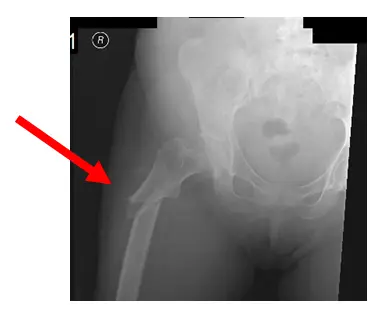

La patiente est une femme de 65 ans qui est arrivée avec une fracture Fosamax du fémur droit. Le patient a également des antécédents d’ostéoporose et prend des bisphosphonates depuis longtemps. L’utilisation chronique de bisphosphonates peut souvent provoquer un retournement osseux, ce qui est une cause fréquente de fractures de Fosamax. Il est typique dans les fractures de Fosamax que la fracture soit sous-trochantérienne et qu’il y ait épaississement du cortex.

Dans ce cas, la fracture du patient est « béante », comme le montre la flèche. Il n’y a pas non plus de renouvellement osseux, ce qui peut conduire au « syndrome des os gelés », ce qui rend cette fracture particulière difficile à guérir. Pour le traitement de la fracture, le patient a subi une fixation interne à réduction ouverte (ORIF) avec augmentation, en utilisant des protéines morphogéniques osseuses.

La radiographie montre une fracture sous-trochantérienne oblique du fémur droit avec angulation latérale.